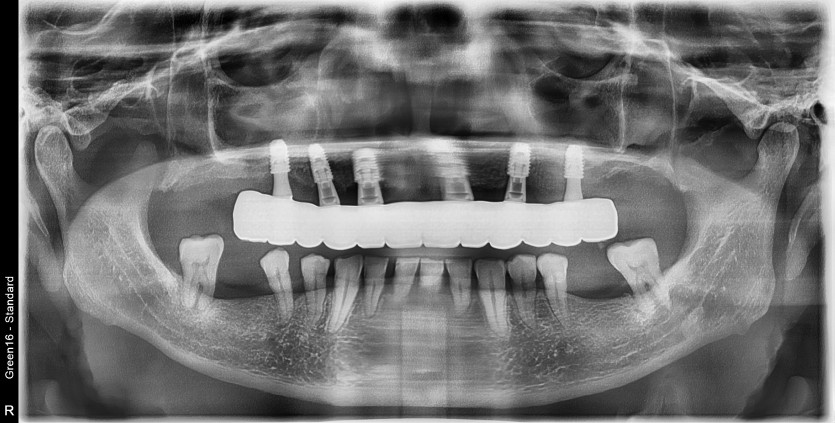

상악 풀아치 임플란트 증례입니다.

6개의 임플란트로 완성하였습니다.